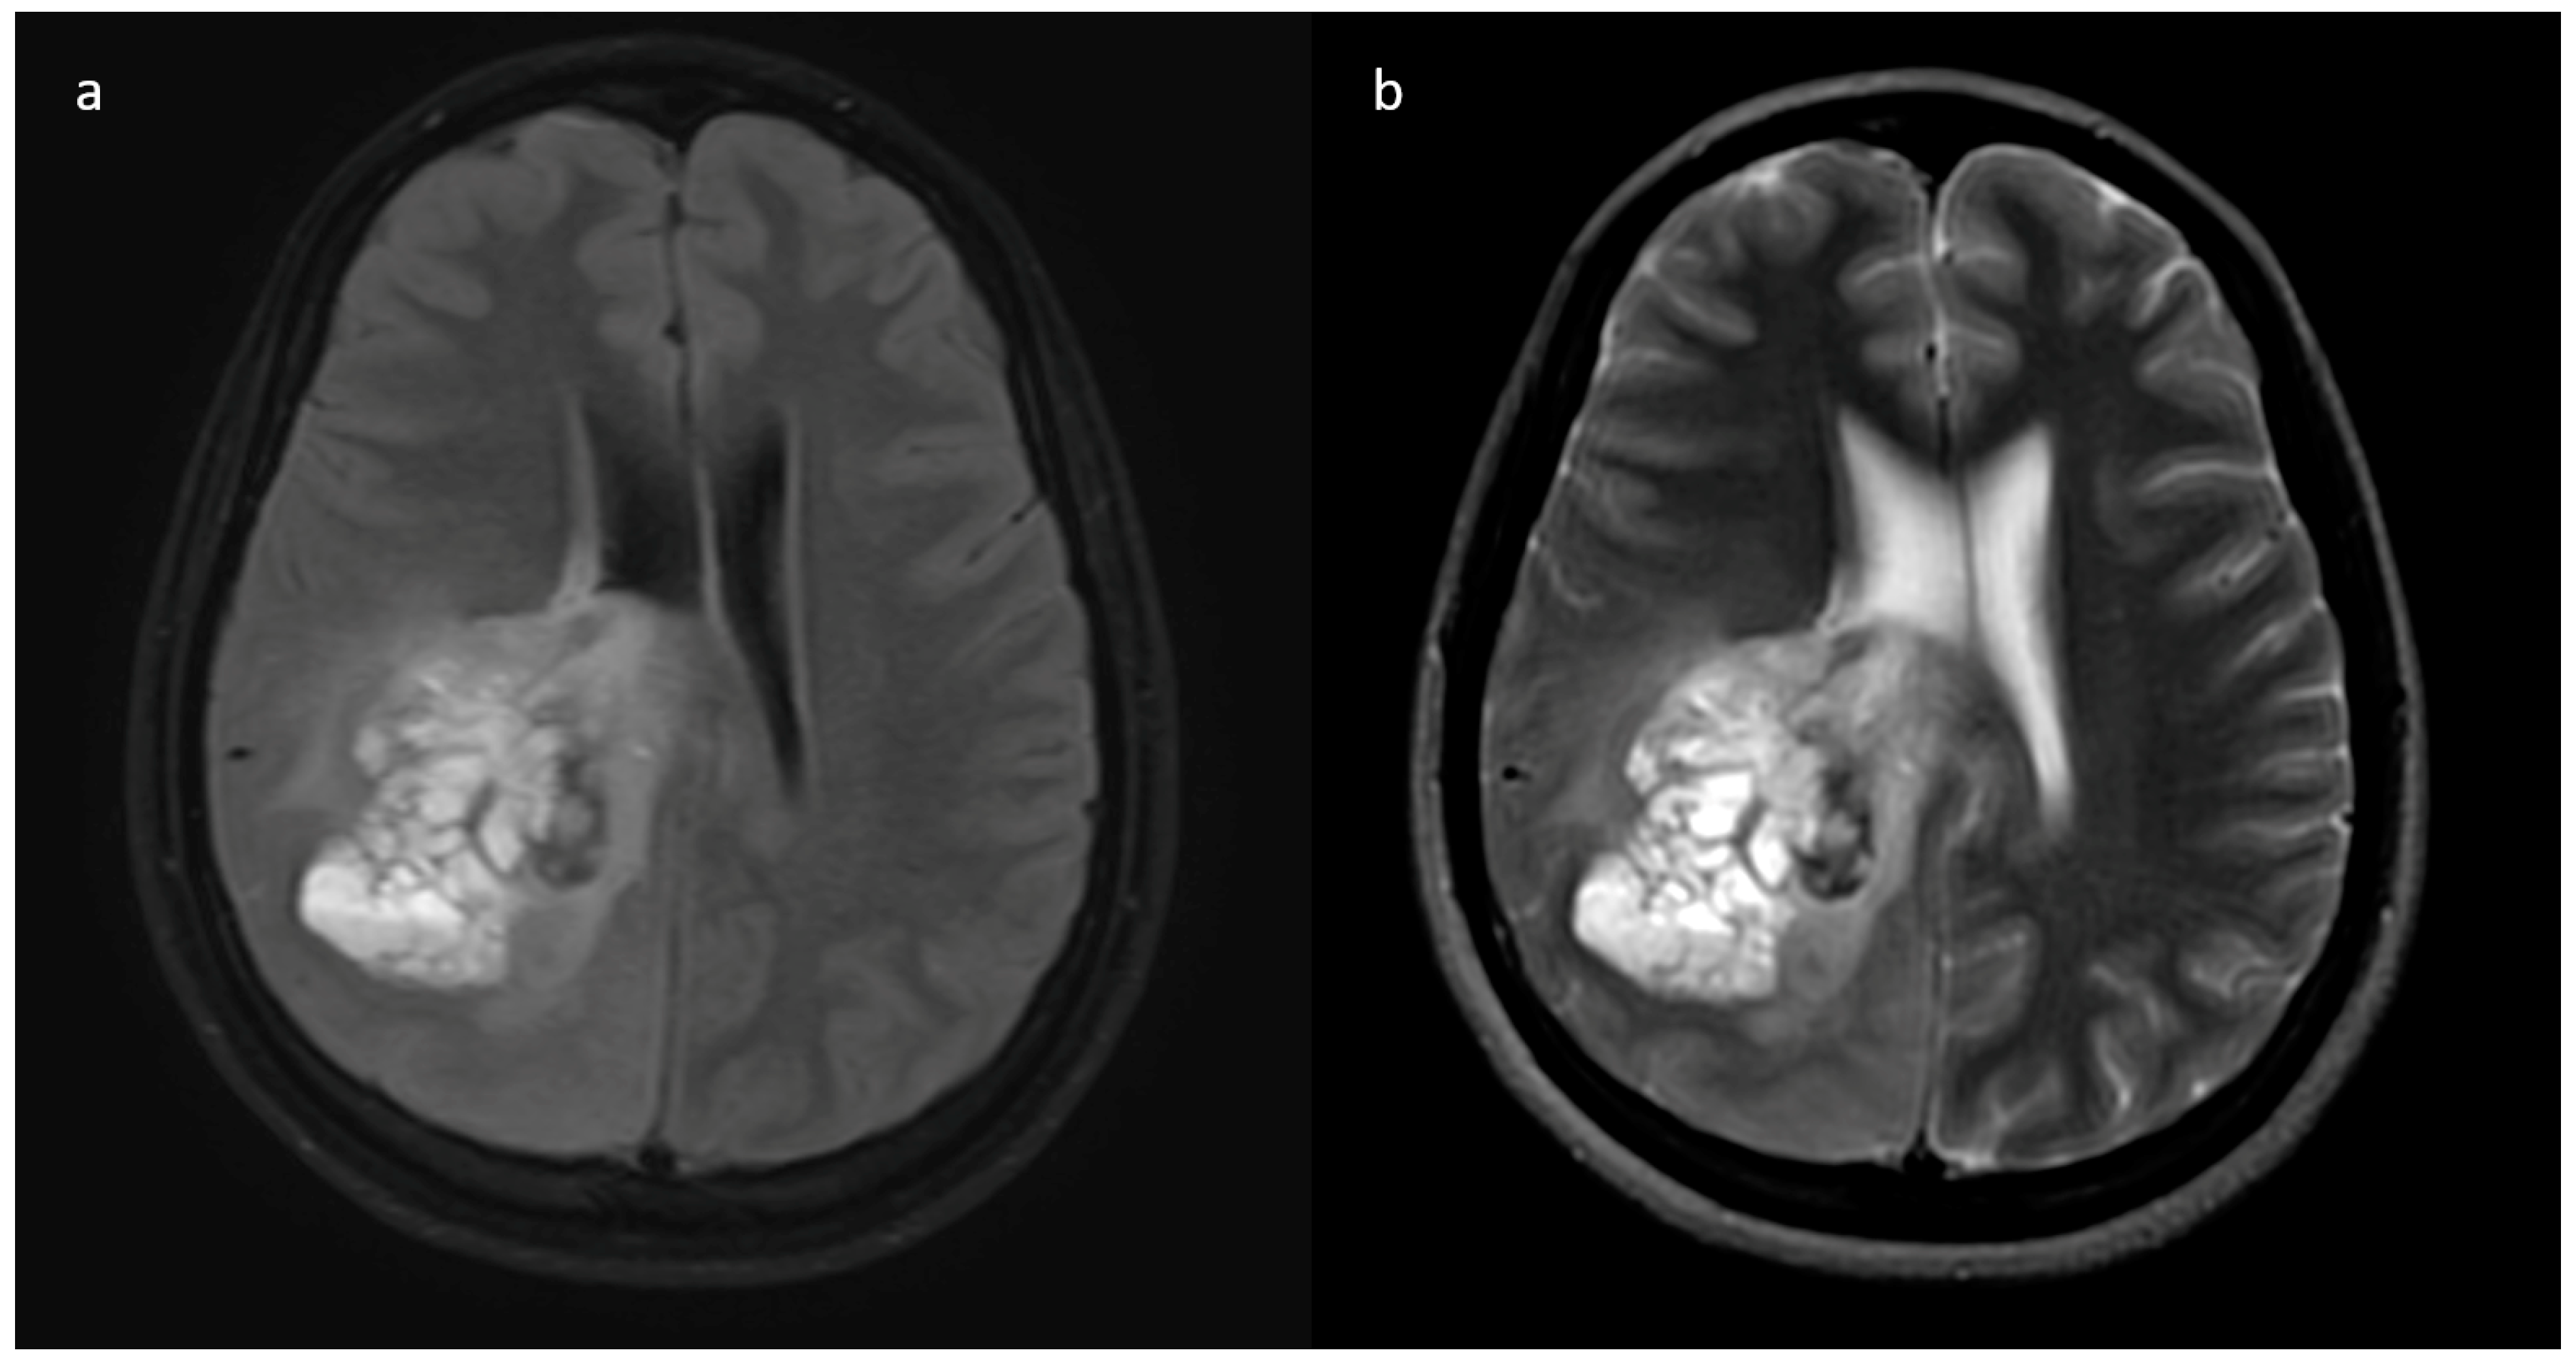

3.2. MRI Parameters of IDH-Wildtype vs. Mutant Phenotype Tumors